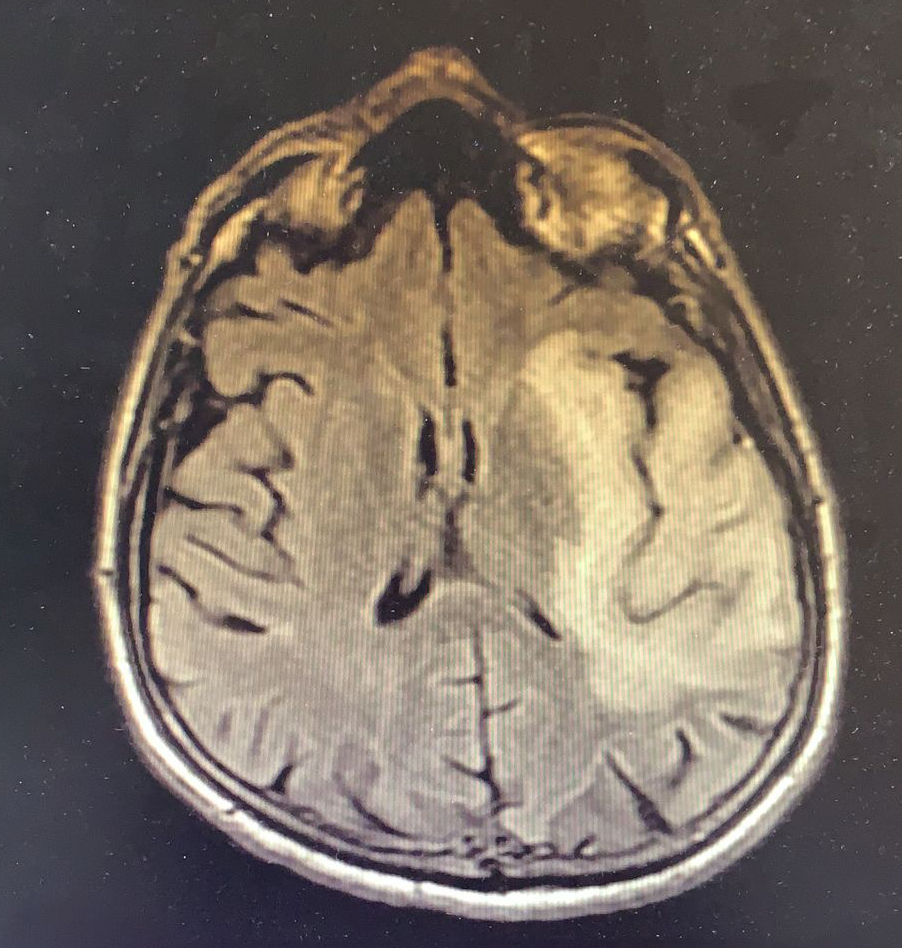

Tedavinin ikinci ayında hasta kliniğimize yaklaşık iki haftadır olan konuşma bozukluğu yakınması ile başvurdu. Fizik muayende genel durumu iyi, şuuru açık, konuşması afazikti. Basit ve tekli emirleri yerine getirebiliyordu. GKS 15 olan hastada sağ kol ve bacakta kas gücü 4/5 idi, duyu defisiti saptanmadı. Yapılan kontrastlı kranial görüntüleme bir önceki kranial MRG tetkiki ile kıyaslandığında eski tetkikte lezyonun insular korteksle sınırlı olduğu güncel incelemede ise kısa sürede belirgin progresif değişiklikler geliştiği şeklinde raporlandı (Resim 2).